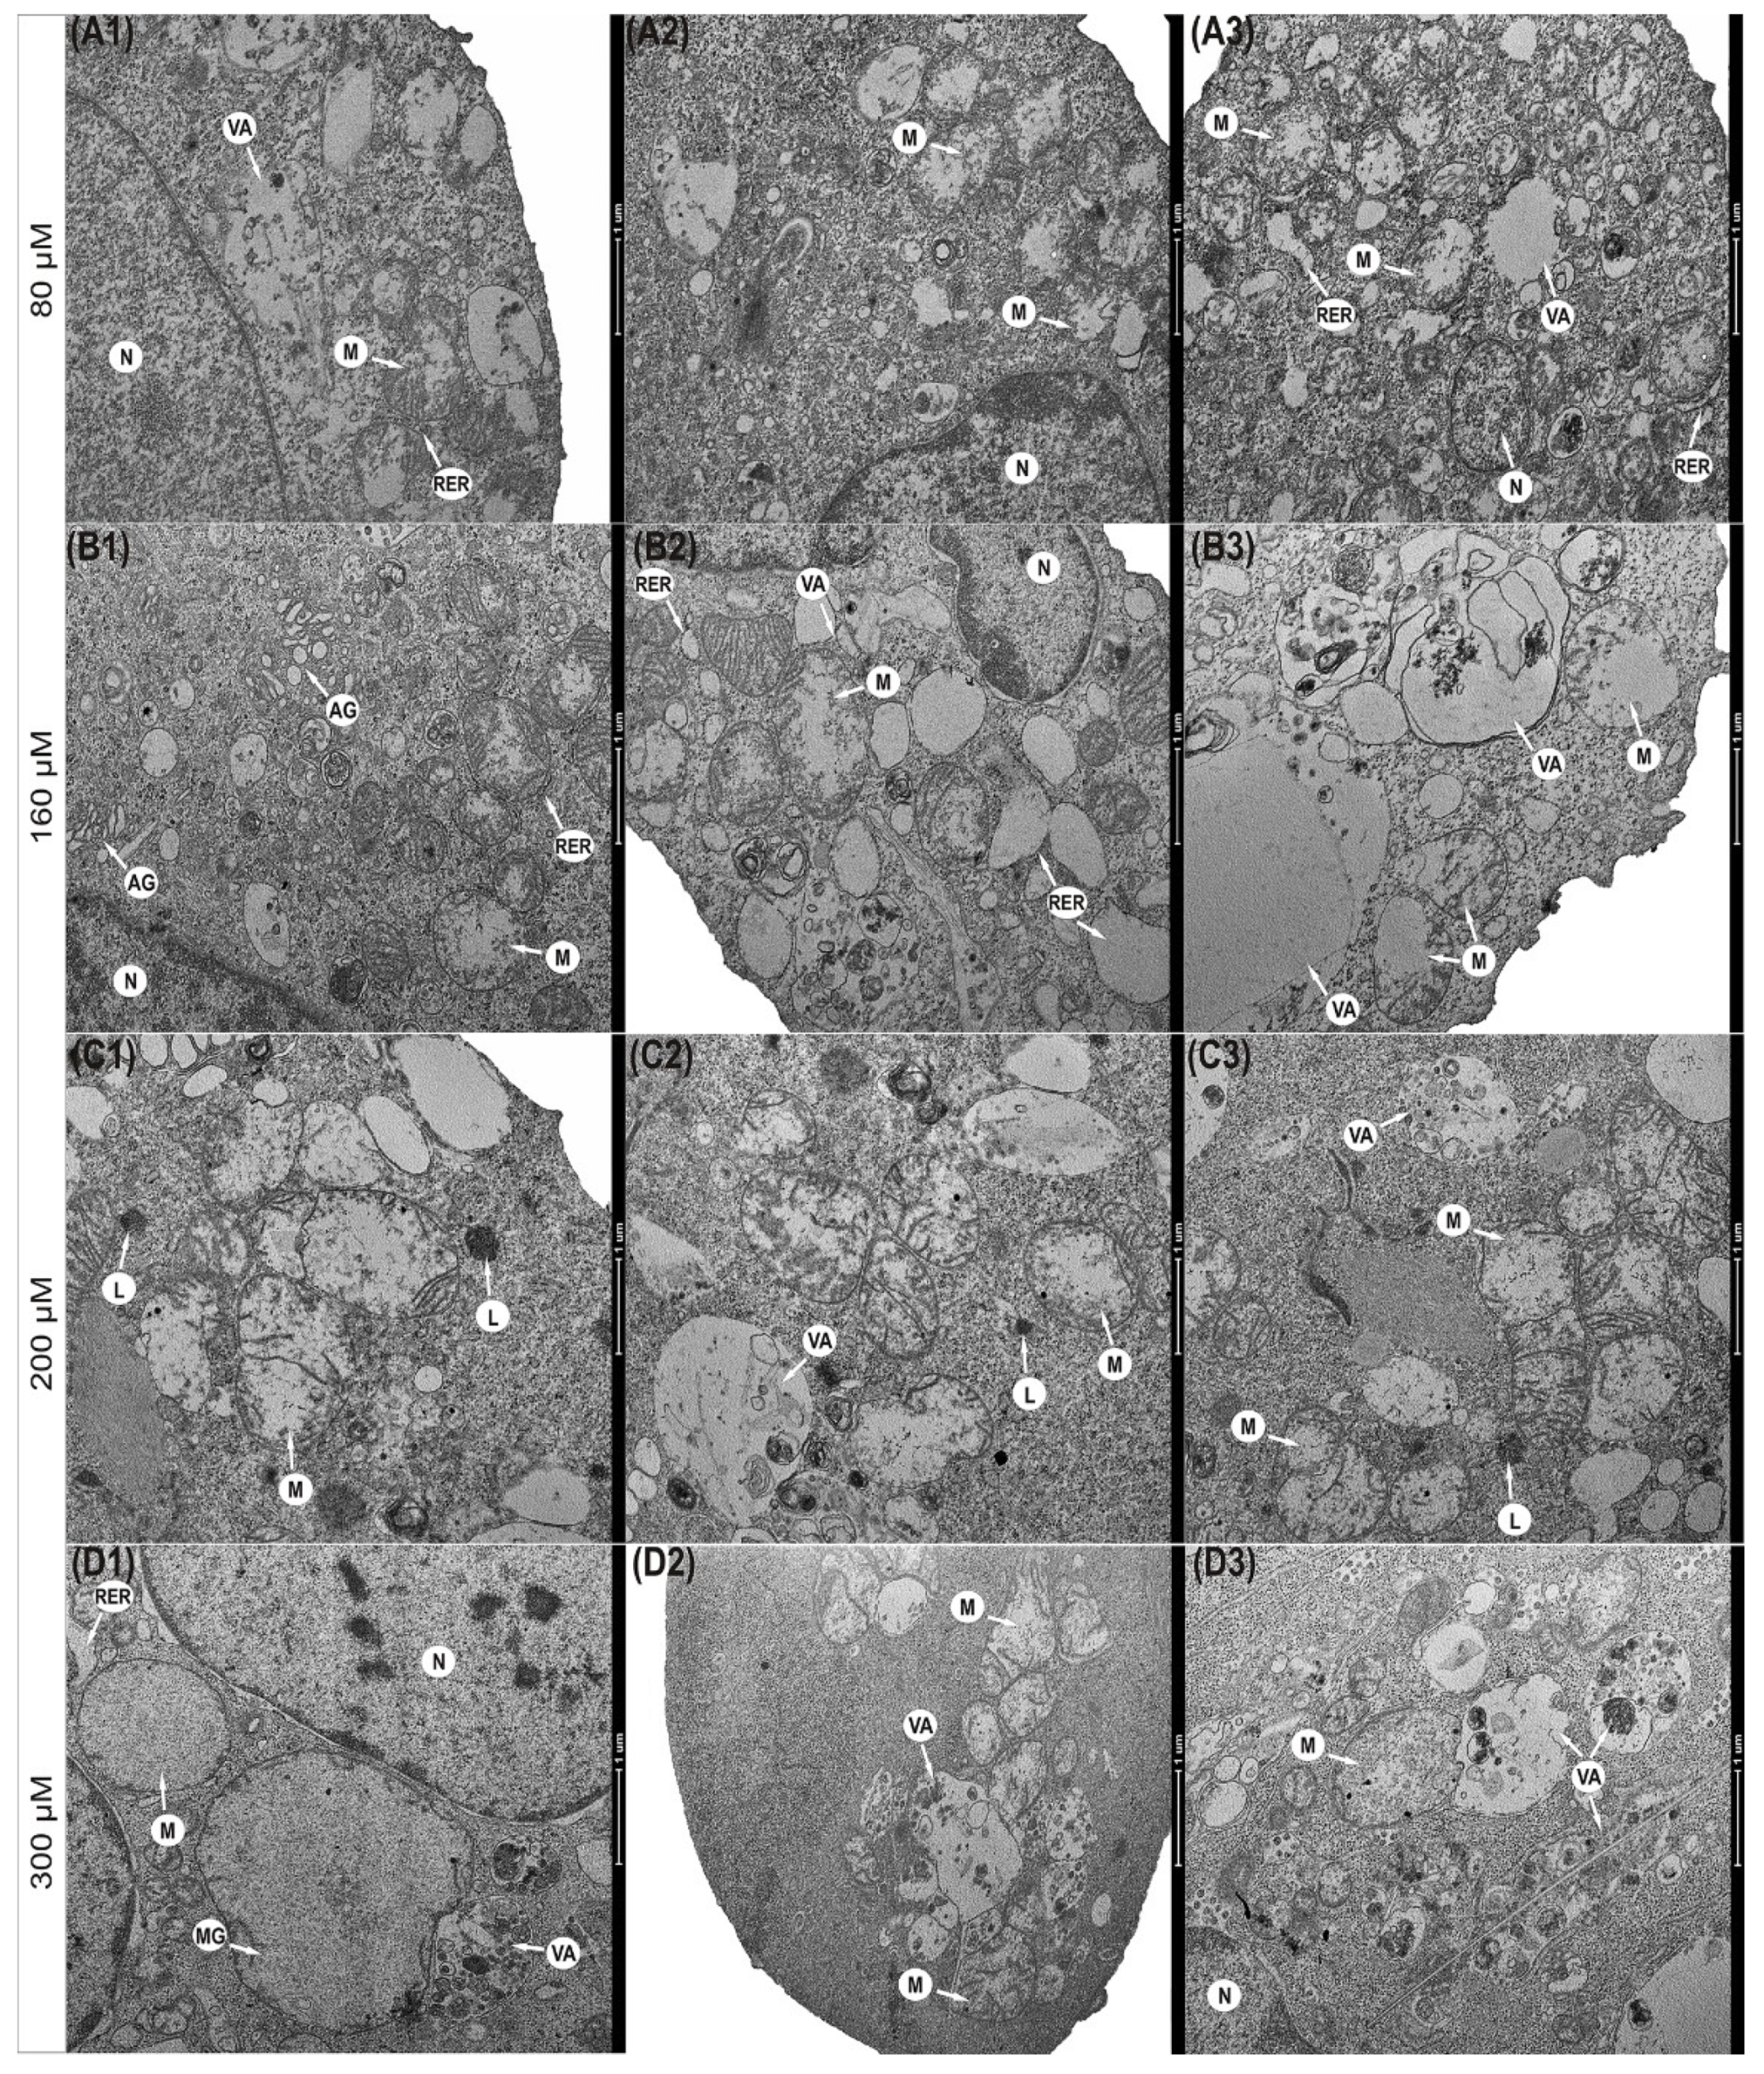

Physcion also caused significant changes in the morphological profile of mitochondria (Figure 3). It was found that mitochondria in the cells exposed to the 80 µM concentration were significantly enlarged with a slight brightening of the matrix (Figure 3(A1–A3)). The concentration of 160 µM anthraquinone caused progressive swelling of mitochondria. Mitochondria had a clear matrix and significantly reduced mitochondrial cristae (Figure 3(B1–B3)). In some mitochondria, interrupted membrane continuity was revealed (Figure 3(B3)). The consequence of the action of physcion at 200 μM (Figure 3(C1–C3)) and 300 μM (Figure 3(D1–D3)) was also a high-amplitude swelling of mitochondria and misplaced cristae. Some mitochondria showed a disruption of the membrane with concomitant leakage of contents into the cytoplasm (Figure 3(C2–C3)). Cells also contained megamitochondria, with a translucent matrix and virtually invisible combs drawn into the swollen membrane (Figure 3(D1)).

Figure 3.

Ultrastructural changes in mitochondria of HeLa cells encumbered for 48 h with physcion. (A1–A3) Cell with swollen mitochondria and dilated channels of rough endoplasmic reticulum (80 µM). (B1–B3) Swollen mitochondria with clear matrix, short cristae (160 µM), mitochondria with membrane rupture and infused into the cytoplasm with 200 µM (C1–C3) and 300 µM (D1–D3). Megamitochondria present in the cytoplasm (D1) (300 µM) with complete loss of mitochondrial cristae. N—Nucleus, M—mitochondria, MG—megamitochondria, AG—Golgi apparatus, RER—rough endoplasmic reticulum, VA—autophagic vacuoles, L—lysosomes. Magnification ×11,500.